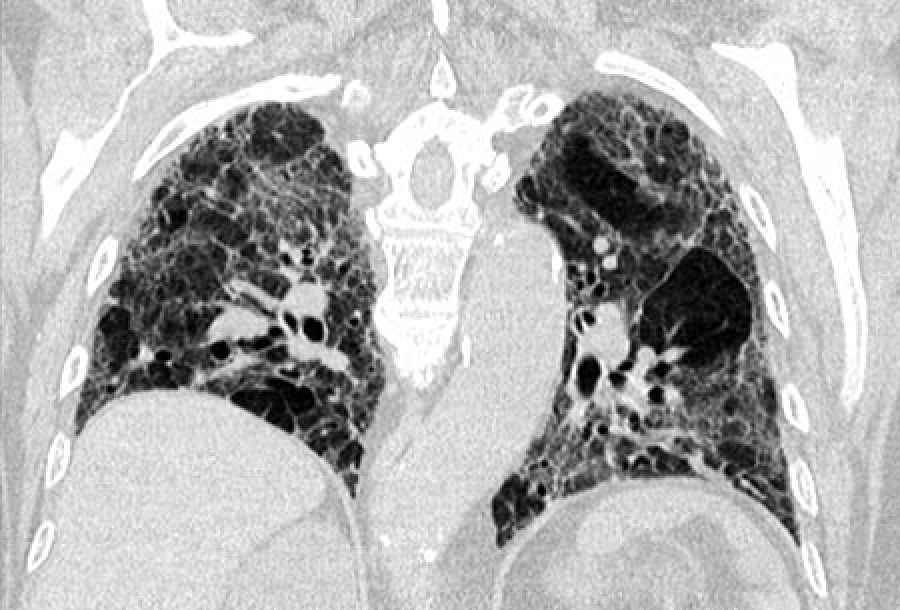

(Fibrosi polmonare idiopatica: Immagine Credit Public Domain).

La fibrosi polmonare idiopatica (IPF) colpisce almeno 32.000 persone nel Regno Unito e rappresenta l’1% di tutti i decessi, con pazienti che hanno un’aspettativa di vita da tre a cinque anni dopo la diagnosi. La malattia causa tessuto cicatriziale che si sviluppa in modo anomalo nei polmoni e riduce progressivamente la capacità di respirare.